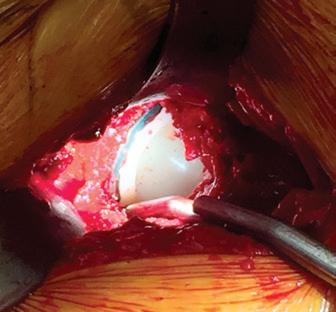

Jig-guided hip revisions

For the first time, Gomina has developed an extraction set that allows a hip revision to be done with minimal bone loss. Thanks to innovative production technologies, it is possible to manufacture dimensionally rigid chisels with different radii. The precision ground, sharp cutting edges of the chisels are the result of Gomina’s many decades of expertise.

The bespoke crafted jigs manufactured by Gomina ensure the application of a precise separation of bone and prosthesis. This innovative pioneering extraction set from Gomina makes surgeon’s work far easier, leading to shorter operating times. Entirely for the patient’s benefit.